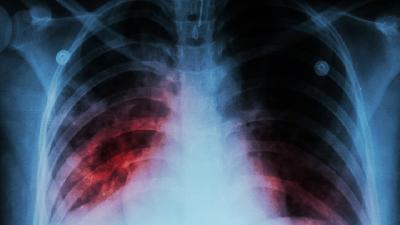

In the consolidated guidelines for tuberculosis (TB) prevention and systematic screening for TB disease, the World Health Organization (WHO) recommends countries with a low TB incidence to consider systematic screening for TB disease as well as testing for TB infection (TBI) and preventive TB treatment (TPT) for migrants from high TB burden countries [1, 2]. Many low TB burden countries, including the Netherlands, perform TB screening among those migrants [3]. In the Netherlands, migrants are mandatorily screened for TB by chest radiography (CXR) within 3 months after entry; migrants from countries with an estimated WHO TB incidence of >200 per 100 000 are also offered voluntary biannual follow-up screening for 2 years.

TB symptom and TB infection screening has potential to replace current chest radiography screening among high TB risk migrants in low burden countries. Screening programmes should be evaluated through epidemiological data and assessing progression rates. https://bit.ly/362r25u